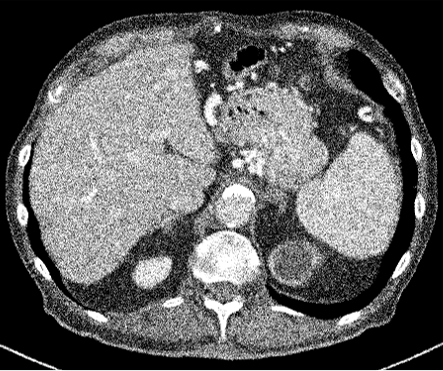

Figure 3: Comparison of existing methods and Ours. (a) LDCT, (b) N2C, (c) N2N, (d) N2V, (e) NDCT, (f) N2C+Ours, (g) N2N+Ours, (h) N2V+Ours.

Table. 1 shows the average PSNR and SSIM scores for supervised and self-supervised methods. Among the compared methods, N2C showed the highest LDCT denoising performance without the proposed techniques; with more significant improvements for all methods when the our methods were applied. Though N2N and N2V report higher scores than NDCT, with similar trends on natural image denoising, they were not very effective when applied to CT. We believe training by merely adding random noise (e.g., Gaussian), often very different from noise observed in CT is not useful for denoising, leading to poor results. Indeed, our method improved every learning method’s performance showing that the technique is model agnostic.

In Figures 2 and 3, we show comparison results of Pseudo-LDCT images and their generated noise using various methods, as well as the predictions of our method for each. In Fig. 2, Pseudo-LDCT images and their noise with Hist and Gaussian highlight a huge discrepancy between the actual LDCT image and its noise. In the case of random noise that is shown to be independently distributed across the entire image, it is often useful for natural image denoising. Moreover, this types of noise does not accurately reflect the nature of CT images. Through the proposed method, we show it is possible to generate Pseudo-CT images that preserve overall CT image characteristics with high quality (Fig. 3).